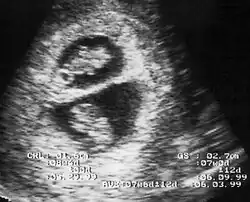

λ Sign in 8 week pregnancy

By performing an obstetric ultrasound at a gestational age of 10–14 weeks, monochorionic-diamniotic twins are discerned from dichorionic twins. The presence of a "T-sign" at the inter-twin membrane-placental junction is indicative of monochorionic-diamniotic twins (that is, the junction between the inter-twin membrane and the external rim forms a right angle), whereas dichorionic twins present with a "lambda (λ) sign" (that is, the chorion forms a wedge-shaped protrusion into the inter-twin space, creating a rather curved junction).[4] The "lambda sign" is also called the "twin peak sign". At ultrasound at a gestational age of 16–20 weeks, the "lambda sign" is indicative of dichorionicity but its absence does not exclude it.[5]

In contrast, the placentas may be overlapping for dichorionic twins, making it hard to distinguish them, making it difficult to discern mono- or dichorionic twins on solely the appearance of the placentas on ultrasound.